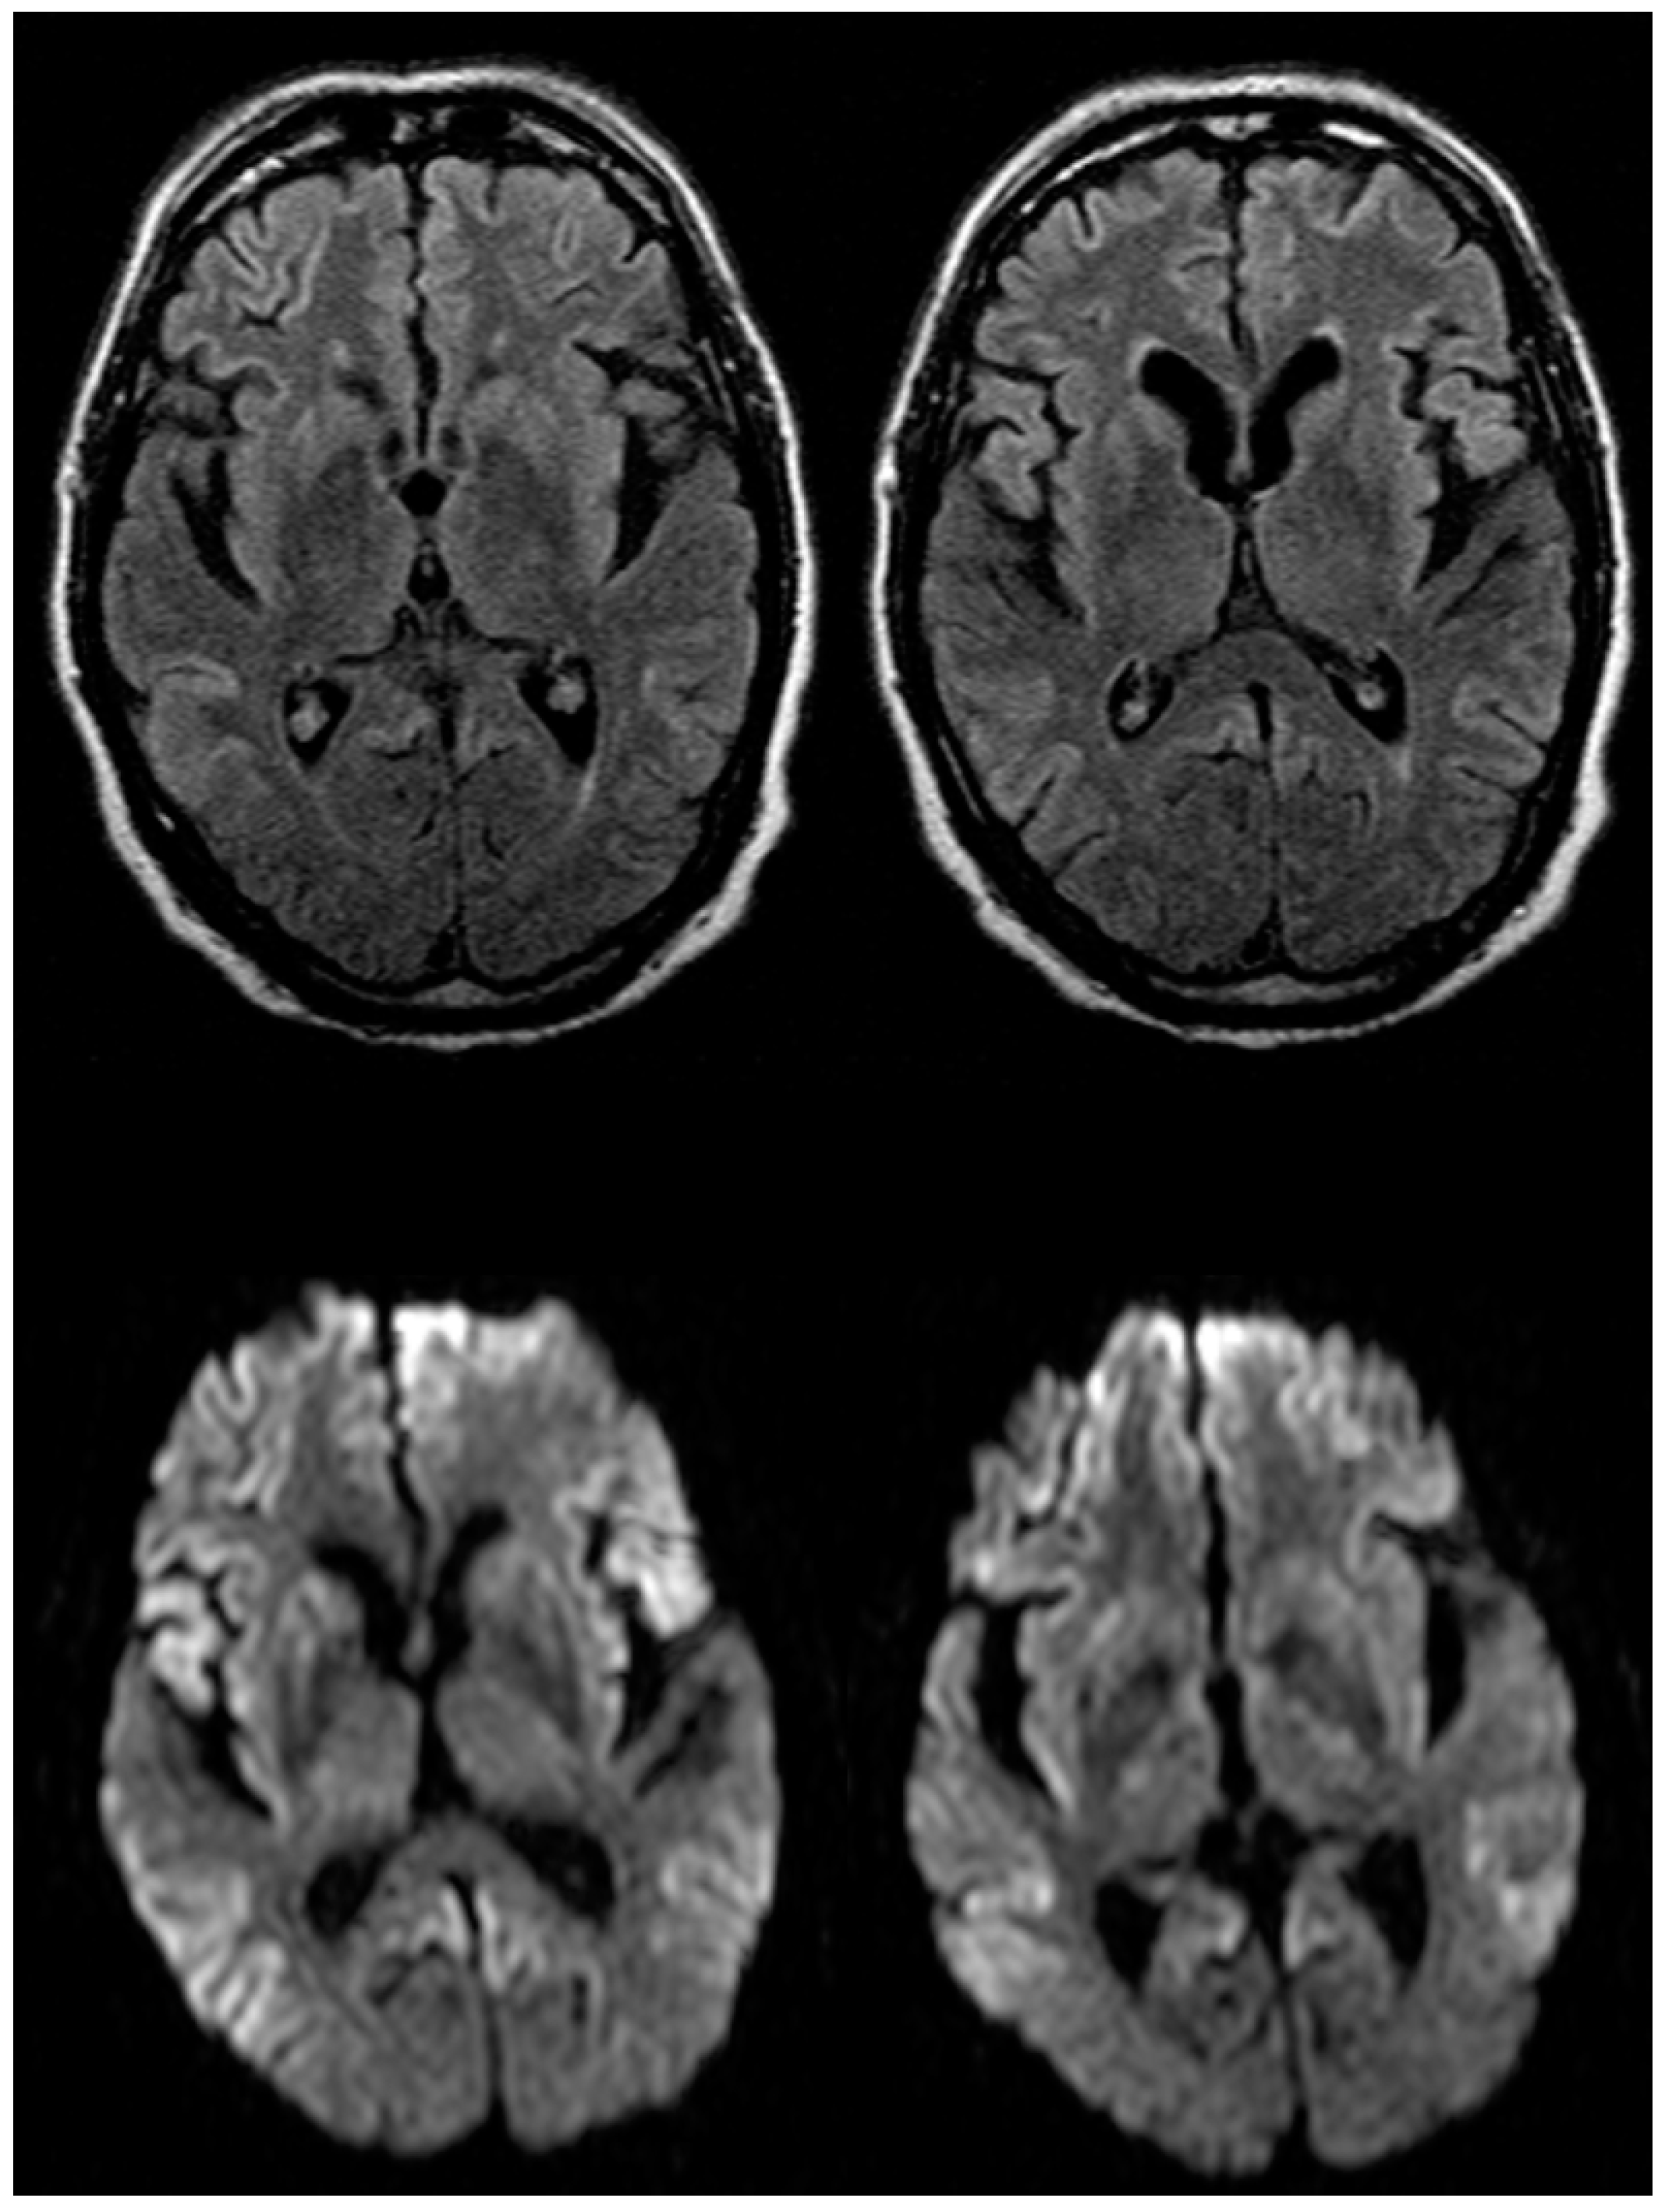

2.1. Case Report